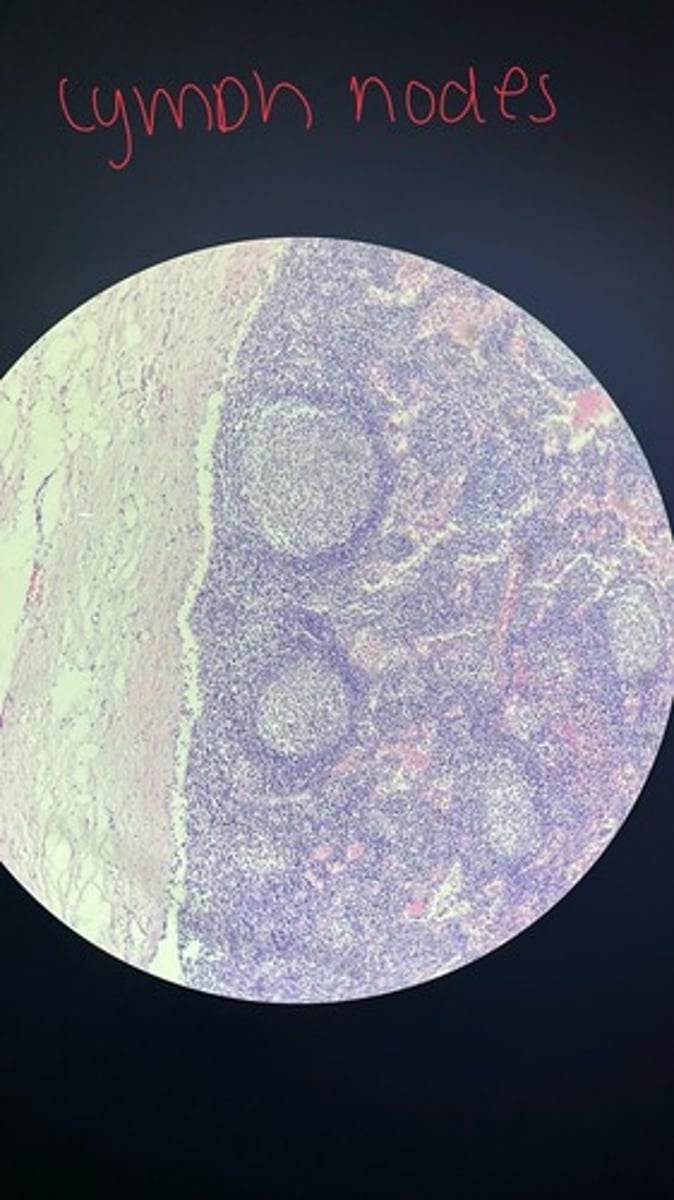

Lymph node HE

Lymph node HE

Lymph node HE

lymph node HE

Lymph node HE

Lymph nodes HE